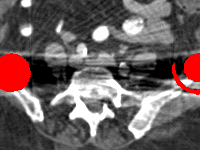

Visual comparison. As shown in Fig. 5, metallic implants such as spinal rods and hip prosthesis cause severe streaky artifacts and metal shadows, which obscure bone structures around them. cGan-CT cannot recover image intensity correctly for both cases. Sinogram domain or dual-domain methods perform much better than cGan-CT. LI, NMAR, and CNNMAR introduce strong secondary artifacts and distort the whole images. In NMAR images, there are fake bone structures around the metals, which is related to segmentation error in the prior image from strong metal artifacts. The segmentation error is also visible in NMAR sinogram. CNNMAR cannot restore the correct bone structures between rods in case 1. The tissues around the metals are over-smoothed in DuDoNet because LI sinogram and image are used as inputs, and the missing information cannot be inferred later. Our model retains more structural information than DuDoNet and generates anatomically more faithful artifact-reduced images.

Visual comparison. Fig. 7 shows two clinical CT images with metal artifacts. Case 1 is with moderate metal artifacts. cGan-CT does not suppress the artifacts completely and generates some fake details. LI, NMAR, CNN-MAR remove all the artifacts but introduce new streak artifacts, which is caused by the discontinuity in the corrected sinogram. DuDoNet outputs over-smoothed sinogram, which leads to blurred tissues close to the metal implants, such as muscle and bone. Only our model can provide realistic enhanced sinogram and remove the artifacts while retaining the structure of nearby tissues. Case 2 is very challenging as the rods bring strong metal shadows and bright artifacts around the vertebra. cGan-CT recovers the shape of vertebra but changes the overall image intensity. Other sinogram inpainting methods fail as the soft tissue and bone near the rods are heavily distorted. Our model removes part of the dark bands and reproduces correct anatomical structures around the rods.